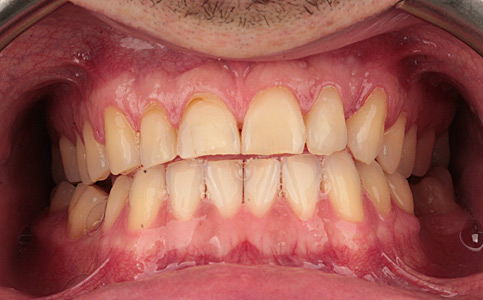

Pacjent zgłosił się do naszej kliniki ponieważ marzył o pięknym uśmiechu. Jego metamorfoza była wielospecjalistyczna. Pierwszym etapem było leczenie biologiczne, następnie uzupełnienie braków zębowych implantami oraz wykonanie koron pełnoceramicznych na zęby górne. Dzięki temu Pacjent odzyskał pewność siebie i zdrowy uśmiech.

Zobacz efekty przeciągając suwak w prawo lub w lewo.